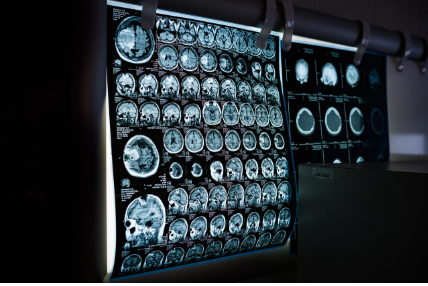

- 혈액검사·MRI·PET 촬영

- 뇌 구조 이상, 뇌혈류 변화 등을 확인